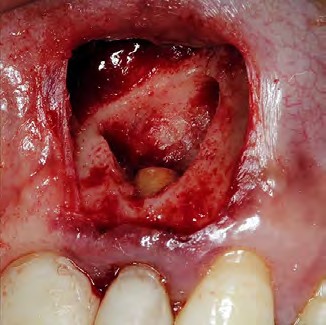

La caja de obturación fue conformada con una punta de ultrasonido P1M (Helse Ultrasonic, Santa Rosa do Viterbo, Brazil) (Fig. 4). La retro-obturación se realizó con Biodentine, preparado según las indicaciones del fabricante (Septodont, Saint Maur de Fossés, France) (Fig. 5), transportado al canal radicular con una espátula de resina y condensado con un microcondensador previo a irrigación por vía retrógrada con Clorhexidina al 2% (Encident clorhexidina, Blenastor ,Quito, Ecuador) aspiración constante y secado con puntas de papel.

Figura 4. Limpieza del campo quirúrgico y caja de obturación.